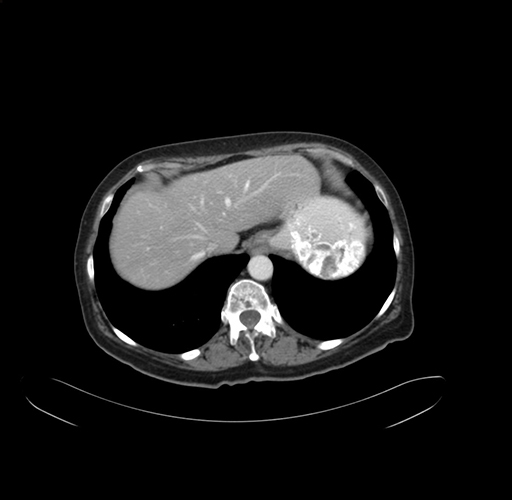

Pre-Chemo: Axial Venous

Axial Venous

Imaging analysis

Based on your CT findings, which issue(s) would give reason for "planned slowing down moment(s)" in this case?